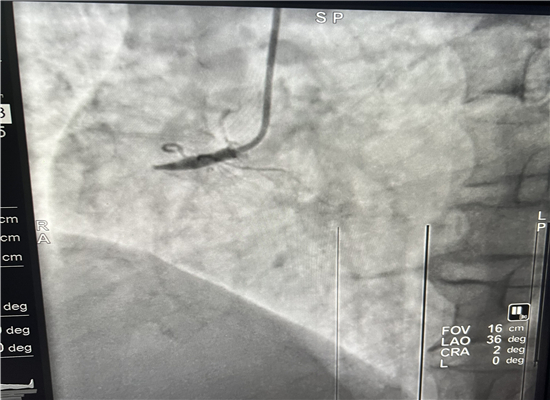

19时13分左右,一名患者因晚饭后行走不稳而请求出诊,急诊医学科医护人员火速赶往现场,到诊时测生命体征,输液后接回急诊医学科,回科后做心电图检查,诊断为急性心肌梗塞,随即通知心血管内科会诊,确定做急诊介入治疗,20时30分进入导管室,杨勇主任、张轩副主任共用21分钟就实现了心肌再灌注,挽救了患者生命。

介入手术前